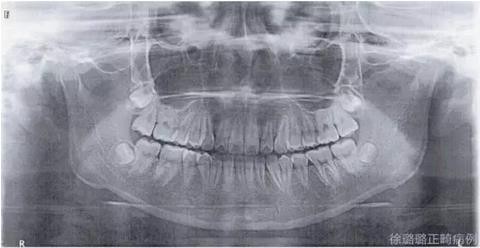

X 線檢查:替牙列,上頜雙側(cè)尖牙埋伏阻生(含牙囊腫),四顆第三恒磨牙牙胚存在。

前牙 CT 檢查:上頜雙側(cè)尖牙埋伏阻生——雙側(cè)尖牙的牙冠均在側(cè)切牙根方的唇向位。